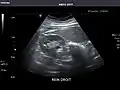

Spleen -